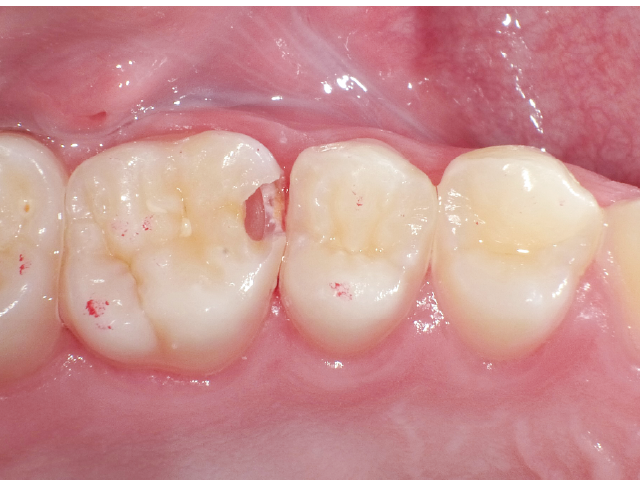

①窩洞形成段階(図1~7)

本症例では、ダイヤモンドの微粒子でコーティングされたエアースケーラーチップを窩洞形態の仕上げに使用。隣在歯の誤切削を防止し、エナメル質の切削断面を歯肉側窩縁までなめらかになるよう仕上げました。

本チップは切削時にストレスが少ない穏やかな振動のエアースケーラー専用のダイヤモンドチップで、切削部となる半球形状の面にのみダイヤモンド砥粒がコーティングされており、背面平坦部は隣在歯を削らないよう平滑になっています(図8、9)。チップの屈曲角度は110°に設定され、窩洞へのアクセスが容易な形状となっています。S67D(アングルの外側)、S68D(アングルの内側)チップは半球状の切削部位が設定され、臼歯部の近遠心両側の窩洞形成に使用が可能です。本症例では、左上6近心隣接面部の窩洞であったため、アングルの外側に半球状の切削部位が設定されている「S67D」を使用しました。これらの器具を使用することにより、頬舌側の隅角部歯質を温存した最小限の規模で窩洞形成を終了、防湿操作および隔壁の設置に移行することができました。